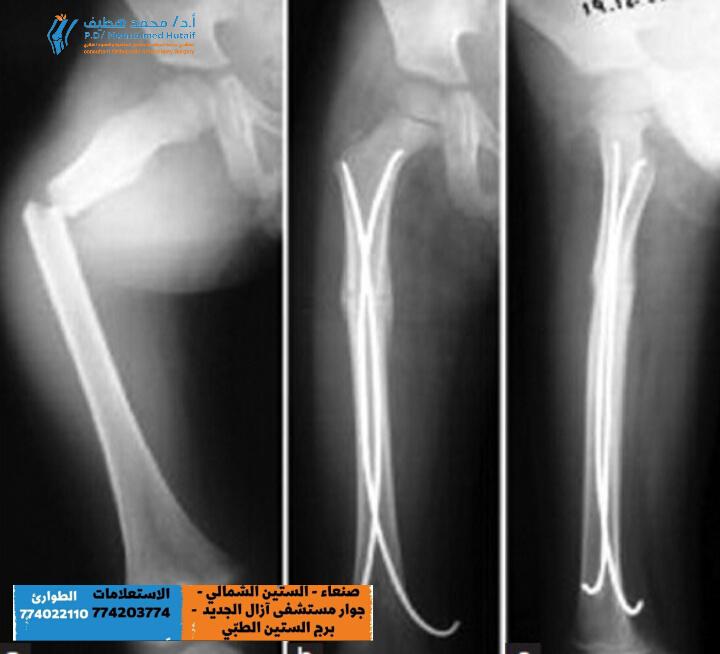

كسور القصبة والشظية عند الأطفال: أنواعها وأسبابها وعلاجها

القصبة والشظية هما العظمان الرئيسيان في الساق، حيث تقع القصبة في الجزء الأمامي والشظية في الجزء الخلفي. كسور القصبة والشظية عند الأطفال هي من أكثر أنواع كسور العظام شيوعًا في هذه المرحلة العمرية،…